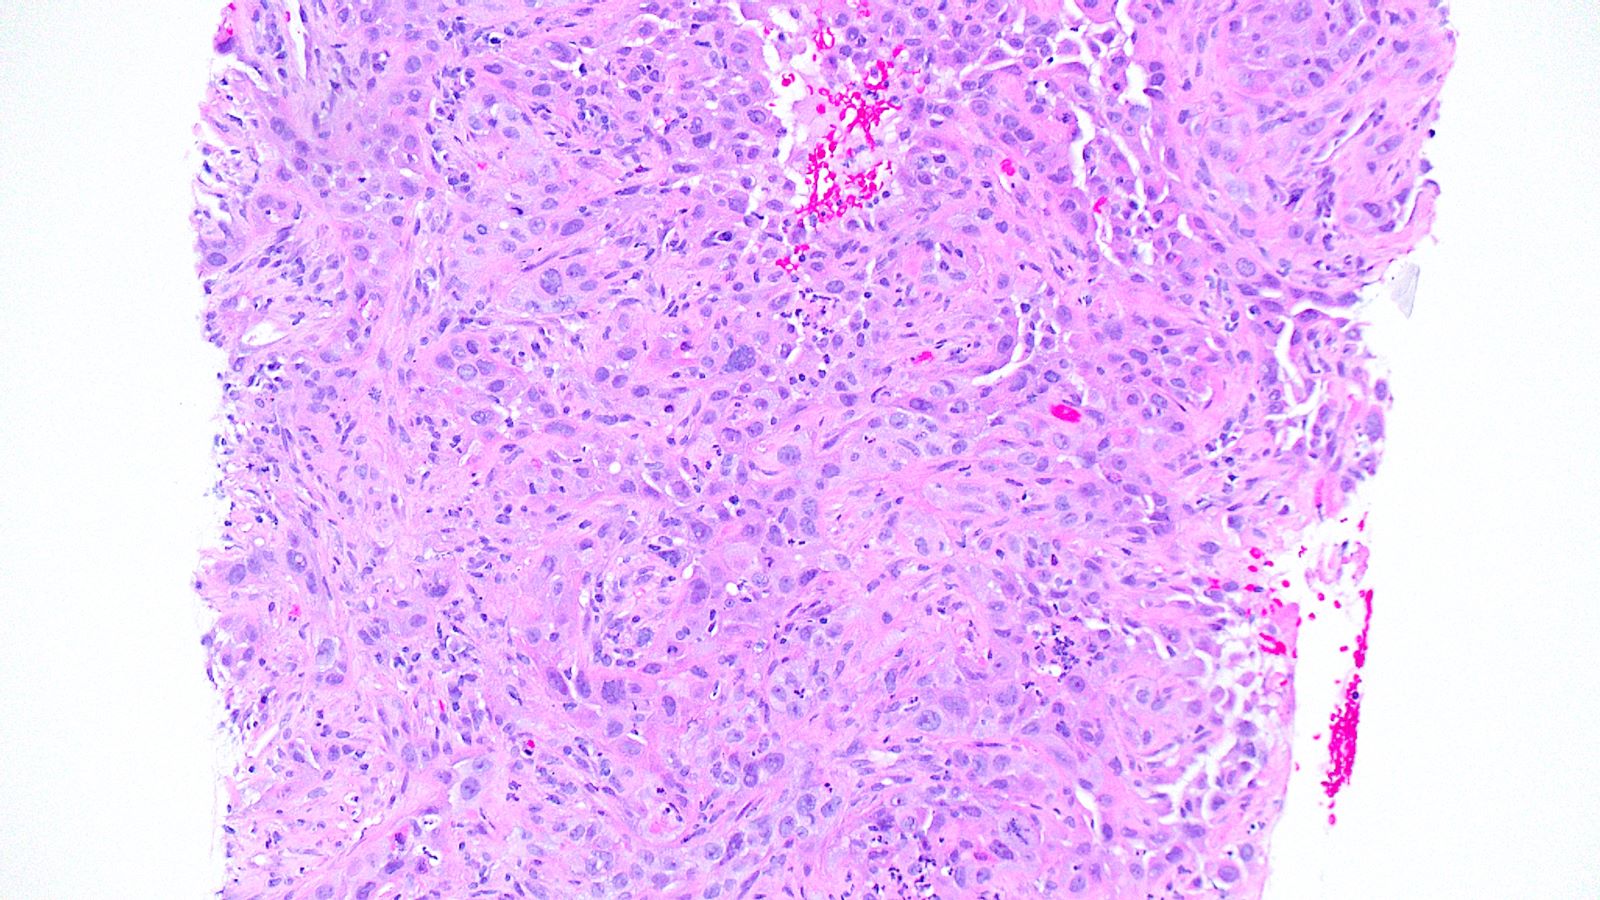

Board review style question #3

A 75 year old man with a 100 pack year smoking history presents with hemoptysis and is found to have a hilar mass and lymphadenopathy. Biopsy of one of the lymph nodes reveals the proliferation seen in the above images. Mitotic activity is approximately 35 mitoses per 2 mm2 and necrosis is present. Immunophenotyping is attempted; however, the block was inadvertently exhausted and stains are not available. What is the best diagnosis that can be rendered?

Board review style answer #3

E. Small cell carcinoma. Small cell carcinoma remains a morphologic diagnosis and does not require immunophenotyping for confirmation. The clinical history and description of the malignant cells are consistent with a diagnosis of small cell carcinoma. Immunophenotyping, including the use of Ki67, is most useful in cases with more ambiguous morphologic features or in crushed biopsies where morphologic features are obscured.